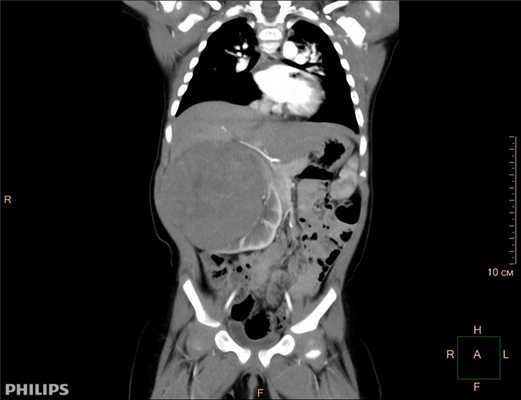

3D-реконструкции опухоли Вильмса пациентов детского отделения НМИЦ онкологии им. Н.Н. Петрова

Опухоль Вильмса. Компьютерная томография